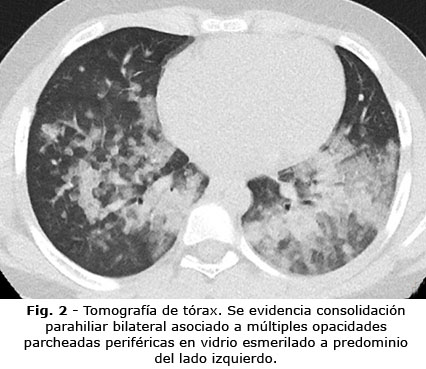

A pesar del soporte de oxígeno, el paciente persistió con taquipnea 60-62 respiraciones/minuto y fiebre 38 °C. Se inició con antibiótico (ceftriaxona 80 mg/kg/día) por sospecha de neumonía bilateral grave de etiología viral o bacteriana. Se cambió de dispositivo a cánula de alto flujo y se realizó una tomografía de tórax (Fig. 2). En la analítica sanguínea se encontró hemoglobina 13,3g/dL, leucocitosis 20,2x103/uL, neutrofilia 16,9x103/uL (sin desviación izquierda), linfocitos 2,2x103/uL, plaquetas 201x103/uL, proteína c reactiva 0,25 mg/dL (valores normales: 0-0,5mg/dL), el perfil renal y electrolitos estaban normal.

La radiografía de tórax es anormal con el transcurso de las horas en un 60 a 90 % de los casos.(1,8) En la tomografía se observan múltiples opacidades y en niños lesiones de tipo consolidación en comparación con los adultos.(9) A pesar de mayor precisión, este examen no está recomendado de inicio porque no modifica el manejo del paciente.(10)